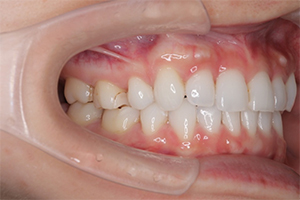

矯正治療のCASE 03

Before

After

- 主訴

- 上下とも歯が出ていて気になる

- 治療内容

- ラビアル矯正(表側)

抜歯あり

- 治療費用

- 88万円~(税込)

- 治療期間

- 18か月

【リスク・副作用】

歯の痛み、口内炎、歯磨きがしにくいことによるむし歯や歯周病のリスク、歯根吸収や歯の変色、後戻りなどの副作用があります。